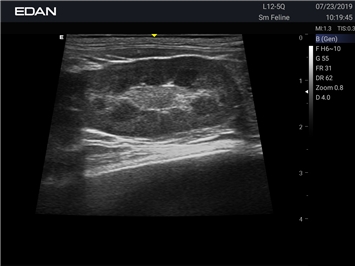

Ветеринарный ультразвук одним нажатием. Система Acclarix AX3 VET разработана с целью обеспечить бескомпромиссную производительность по доступной цене. Наличие уникальных двойных разъемов и двойных аккумуляторов в легком корпусе массой 4,5 кг из магниевого сплава позволяет системе Acclarix AX3 VET удовлетворять все потребности ветеринарных исследований, сохранив низкую стоимость.

EDAN Acclarix AX3 VET - это компактная ультразвуковая система, специально разработанная для ветеринарной практики, сочетающая высокую производительность с доступной ценой.

• Революционная платформа с превосходным разрешением для глубоких структур

• Специальные настройки для исследования животных разных видов

• Специализированные предустановки для ветеринарных исследований